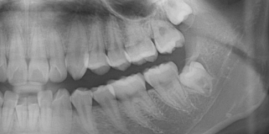

这是非常重要的一个获取空间的方式,可以看到很多牙齿唇倾、牙齿不齐的孩子,从片子上看,她的牙齿都是近中倾斜的,当把牙齿向后直立,每直立10度会获得1.5毫米的空间,如果直立4颗牙那就是6毫米。